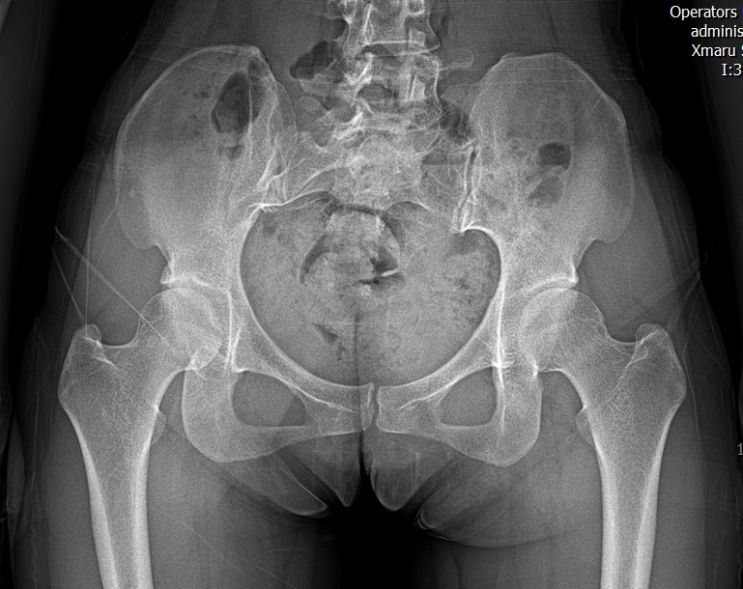

x-rayㅣ좌골이 컨택이 안된다?

24. 05. 30일 내 골반 아래 사진과 비교했을때 normal로 보여짐. 모빌리티 주기 힘든 case 네모난 박스 형...